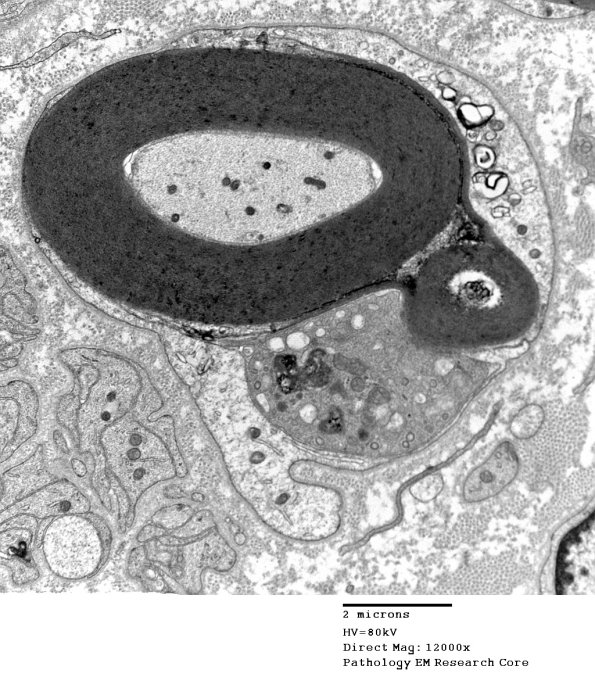

1D16 CIDP  (Case 1) EM 037 - Copy

Another early stage of macrophage infiltration. (electron micrograph)